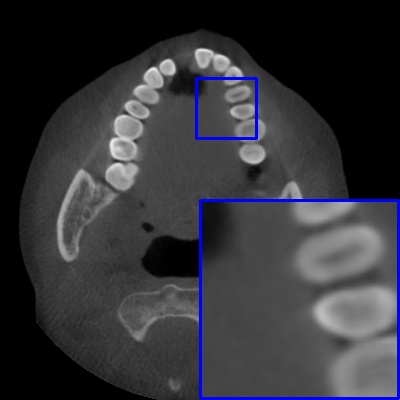

Figure 3: Visual comparison of MAR images by different methods on synthetic MA image. The PSNR (dB)/SSIM results are reported below each image for reference.

Results on synthetic MAR. In Table 1, we provide the quantitative results. One can see that our MARformer-L outperforms the other methods in terms of PSNR and SSIM, but needs only 11.76M parameters and 60.25G FLOPs. Note that the second best method Uformer-B has 50.42M parameters and 205.82G FLOPs. Besides, our MARformer-T achieves similar PSNR and SSIM results with Uformer-T, but needs only 0.40M parameters and 12.82G FLOPs compared to 5.24M and 25.39G for Uformer-T. Our MARformers also achieves faster inference speeds than the Uformers, though with inferior Dice scores, respectively. The qualitative results of visual quality are presented in Fig. 3. We observe that our MARformer-L well recovers the teeth shapes and obtains higher PSNR and SSIM results than the other comparison methods. The light-weight MARformer-L achieves similar results to Uformer-T. All these results validate that our MARformer is more efficient than the comparison methods on dental CBCT MAR.